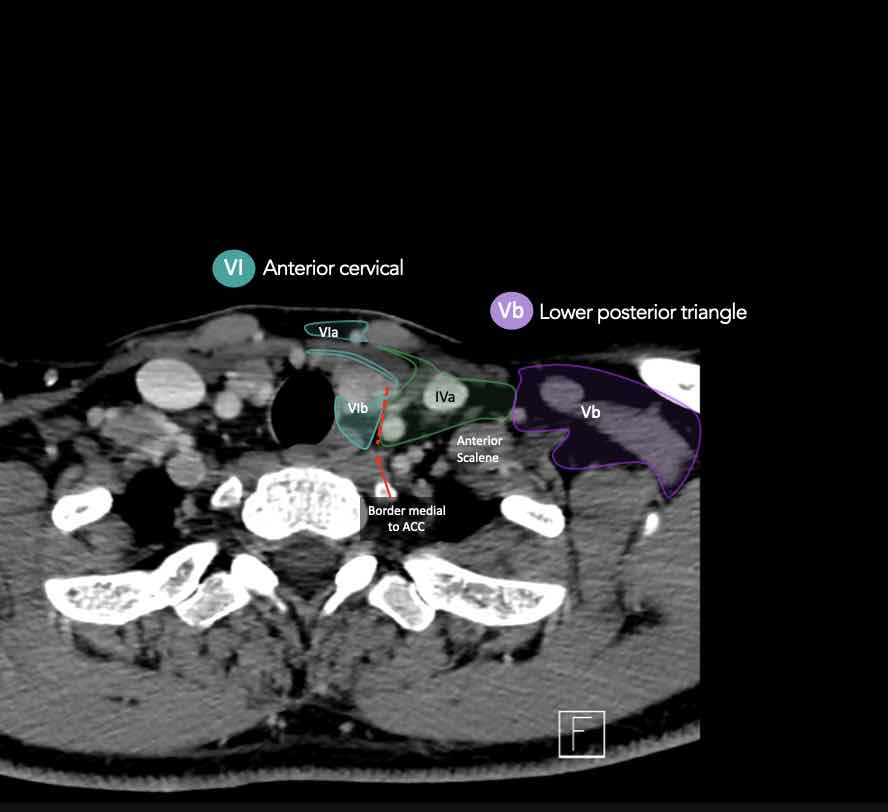

CT Scan Mặt Cắt Ngang (Axial CT)

Các lát cắt CT mặt phẳng ngang tương ứng với hình minh họa tổng quan.

Các lát cắt CT mặt phẳng ngang với hình ảnh chi tiết hơn.

Nhấp vào hình ảnh để phóng to.

IV – Tĩnh mạch cảnh dưới và hố thượng đòn trong

Ranh giới giữa tầng IVa và IVb được xác định tùy ý tại vị trí 2 cm phía trên khớp ức đòn.

VI – Cổ trước

Tầng này chứa các hạch tĩnh mạch cảnh trước nông (tầng VIa) và các hạch sâu hơn bao gồm hạch trước thanh quản, trước khí quản, cạnh khí quản và hạch thần kinh thanh quản quặt ngược (tầng VIb).